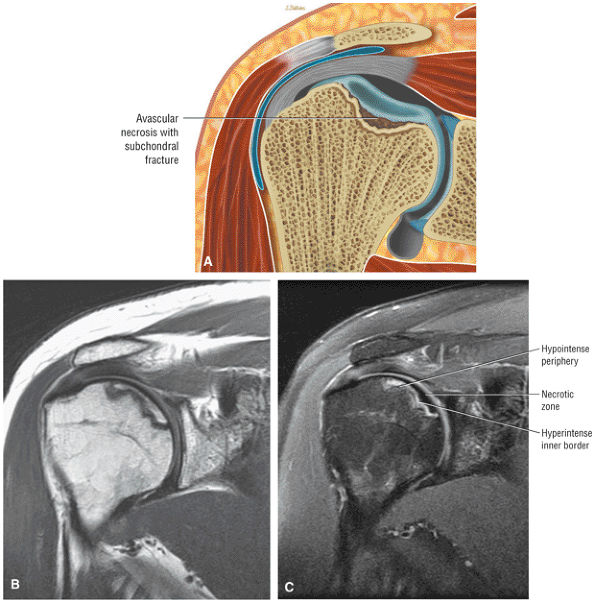

FIGURE 8.102 ● (A) The anterior undersurface of the acromion and the coracoacromial ligament form the coracoacromial arch. The subacromial subdeltoid bursa facilitates the passage of the rotator cuff and proximal humerus under the coracoacromial arch. (B) A superior axial image shows the anterior-to-posterior extent of the coracoacromial (CA) ligament perpendicular to the supraspinatus tendon. The fluid in the subacromial-subdeltoid bursa represents fluid between two serosal surfaces in contact with each other. One serosal surface is contributed by the undersurface of the coracoacromial arch and deltoid, and the other serosal surface is on the bursal side of the cuff.

|

![]() |

FIGURE 8.103 ● Pseudospur. The normal broad attachment of the coracoacromial ligament to the inferior surface of the acromion is shown on (A) T1-weighted coronal oblique and (B) sagittal oblique images. The low-signal-intensity acromial cortex (black arrows) and adjacent coracoacromial ligament and lateral slip of the deltoid attachment (white arrows) give the false impression of a small subacromial spur in the coronal plane. This pseudospur should not be misinterpreted as impingement; otherwise, unnecessary acromioplasties may be performed on patients with a normal coracoacromial ligament attachment and no associated acromial spurs.